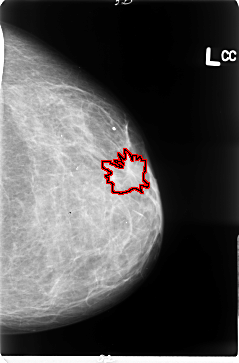

B_3047_1.LEFT_CC

LEFT_CC LINES 4712 PIXELS_PER_LINE 3104 BITS_PER_PIXEL 12 RESOLUTION 50 OVERLAY

FILE: B_3047_1.LEFT_CC.OVERLAY

TOTAL_ABNORMALITIES 1

ABNORMALITY 1

LESION_TYPE MASS SHAPE IRREGULAR-ARCHITECTURAL_DISTORTION MARGINS OBSCURED-ILL_DEFINED-SPICULATED

ASSESSMENT 4

SUBTLETY 3

PATHOLOGY MALIGNANT

TOTAL_OUTLINES 1

BOUNDARY